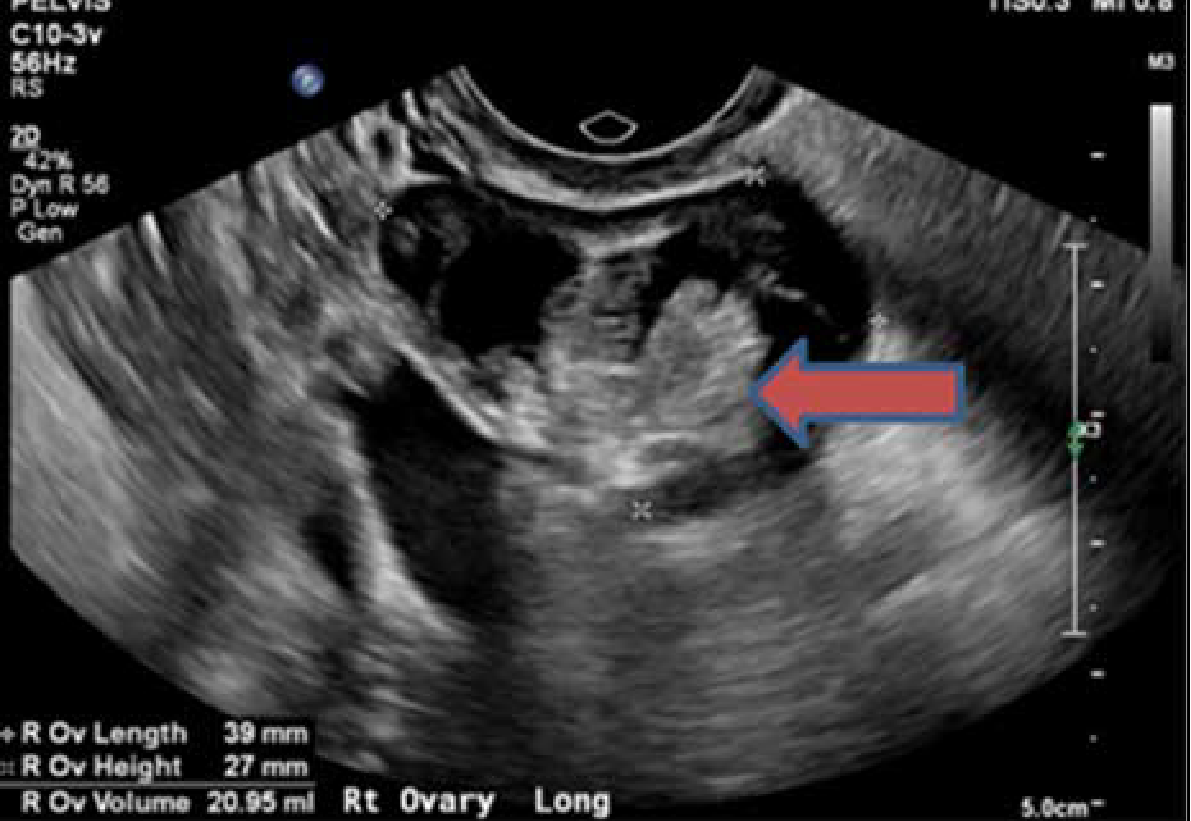

然而,患者血清抗NMDA受体抗体回报阳性。关键是,患者的盆腔超声及MRI提示右侧卵巢肿块,与囊性畸胎瘤表现一致。上述发现确认了抗NMDA受体脑炎的诊断。

图1 盆腔超声发现右侧卵巢肿物,符合囊性畸胎瘤表现